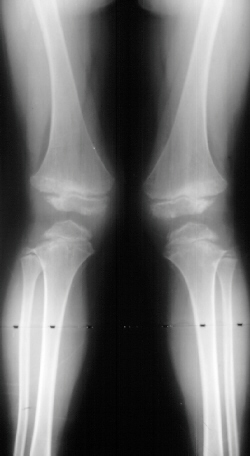

An 11 year old white male presented with a diagnosis of Multiple Epiphyseal Dysplasia (MED). Initially he presented with x-rays revealing mild genu valgum (image1) which progressed (image2) such that he required surgery. He had a supracondylar osteotomy which was performed in 1993 for genu valgum(image3). Two years later he was last seen for low back pain.